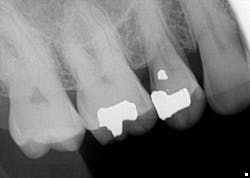

A radiograph assessment revealed a slight radiolucency at the apex of the palatal root on tooth No. 3 (figure 8). Biting and percussion was WNL; probing depths were 6 mm interproximal and 3–4 mm on the facial/lingual. Cold and electric pulp tests were negative. The vestibular area in the No. 3–4 area was tender to palpation. Clinically, a large fracture line was noted on the lingual and on the distal marginal ridge (figure 9).

Diagnosis: Necrotic No. 3 with likely association of extended fracture line into the pulpal space. Recommendations were given to the patient, who opted for extraction and eventual implant placement. Upon removal of the tooth, the following was noted (figure 10):

Testing of the upper right side was, for the most part, inconclusive, aside from some 6 mm pockets in the upper right quadrant. Radiograph was WNL (figure 11). A potential sinus infection was discussed, along with the possibility of a periodontal abscess. The patient was placed on antibiotics, referred to an ENT, and had scaling and root planing done on the upper right quadrant.

The report from the ENT was negative. The symptoms persisted and, in fact, started to worsen. The likelihood of a vertical root fracture was then discussed with the patient. He was referred to an endodontist who took a CBCT scan.

Evaluation by the endodontist showed a very small direct, vertical 9 mm drop on the lingual with radiolucency on the lingual root in the scan about halfway down (figure 12). Given the history of the double root canal, symptoms, and radiographic evidence, it was concluded that the patient had sustained a vertical root fracture on the lingual root of tooth No. 4. Prognosis was poor, and the tooth was removed with discussion regarding replacement options.